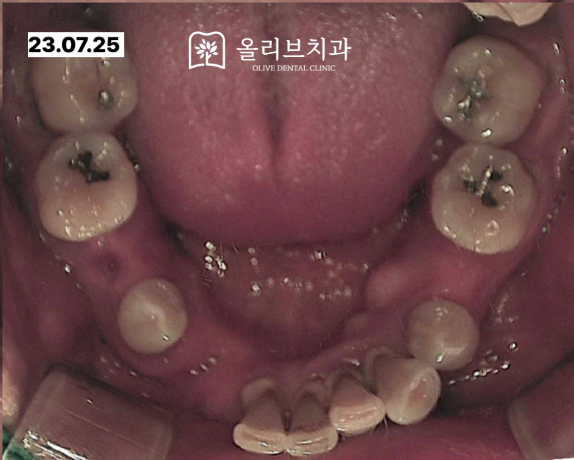

입 안에서도 살펴보면 남아있는 치아에는 치석이 많이 쌓여있어서 치주상태가 좋지 않은 것을 확인할 수 있습니다.

저희병원에 처음 내원하셨을 때의 정면 모습입니다.치아가 없는 부위가 관찰되고 잇몸이 많이 함몰되어 있는 것을 확인할 수 있습니다.